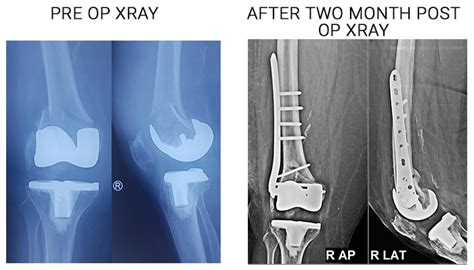

Best Joint Replacement Surgeon in Delhi